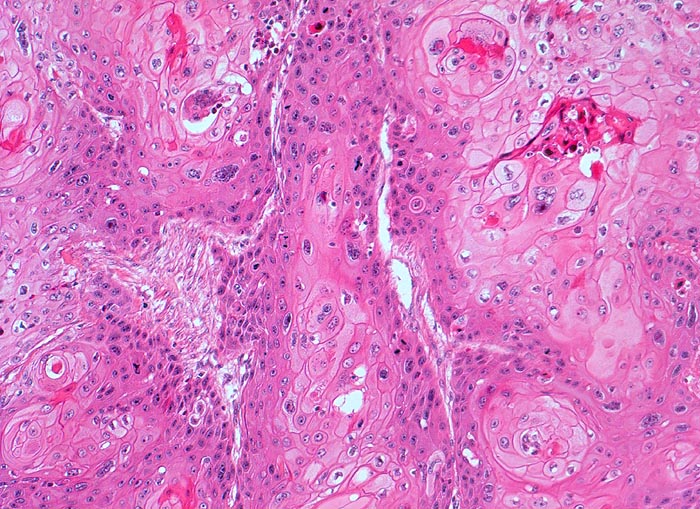

PathoPic – image database / PathoPic ID 3230 - Verhornendes Plattenepithelkarzinom

Verhornendes Plattenepithelkarzinom

Harnblase

Solide plattenepithelial differenzierte Tumorzellstränge. Einige Tumorzellnester zeigen im Zentrum Verhornungszeichen. Zahlreiche Mitosen. Tumorzellen mit ausgeprägter Zellkernpolymorphie und reichlich eosinophilem Zytoplasma. Deutliche Zellgrenzen.

Plattenepithelkarzinome treten als Folge chronischer Entzündungen auf. (Dauerkatheterträger, Zyklophosphamid Langzeittherapie mit Zystitis, Bilharziose).